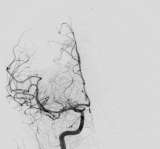

Cerebrovascular Program

UCLA is an international referral center for complex neurovascular disorders of the brain and spinal cord. A multidisciplinary team consisting of cerebrovascular neurosurgeons, interventional neuroradiologists, stroke neurologists and radiation oncologists collaborate closely to design individualized treatment plans combining optimal therapies for each patient's unique needs.